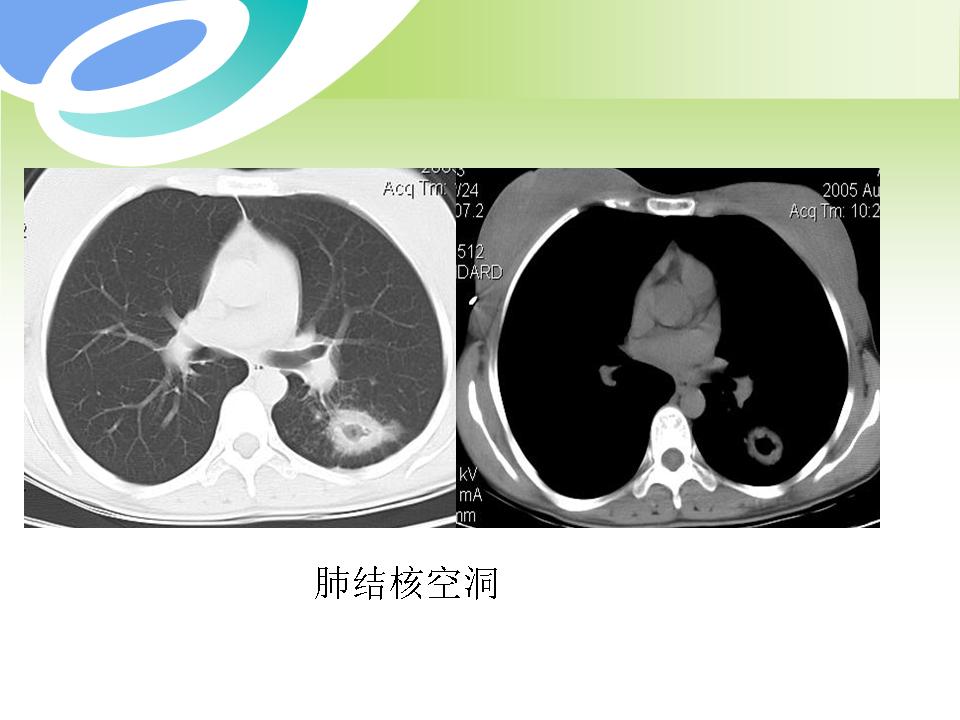

肺部病变的CT基本征象